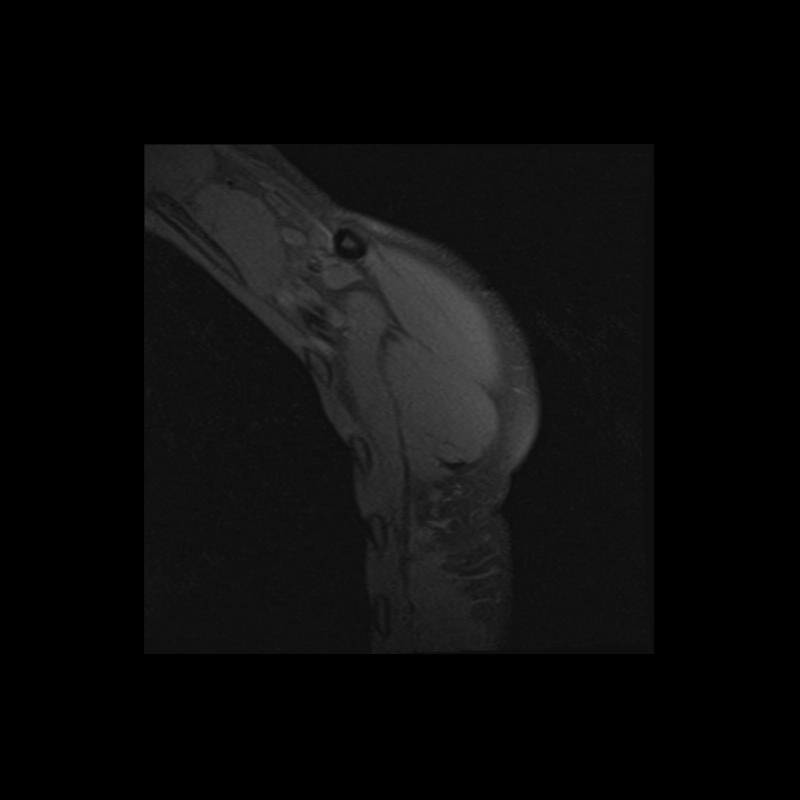

Shoulder MRI Anatomy